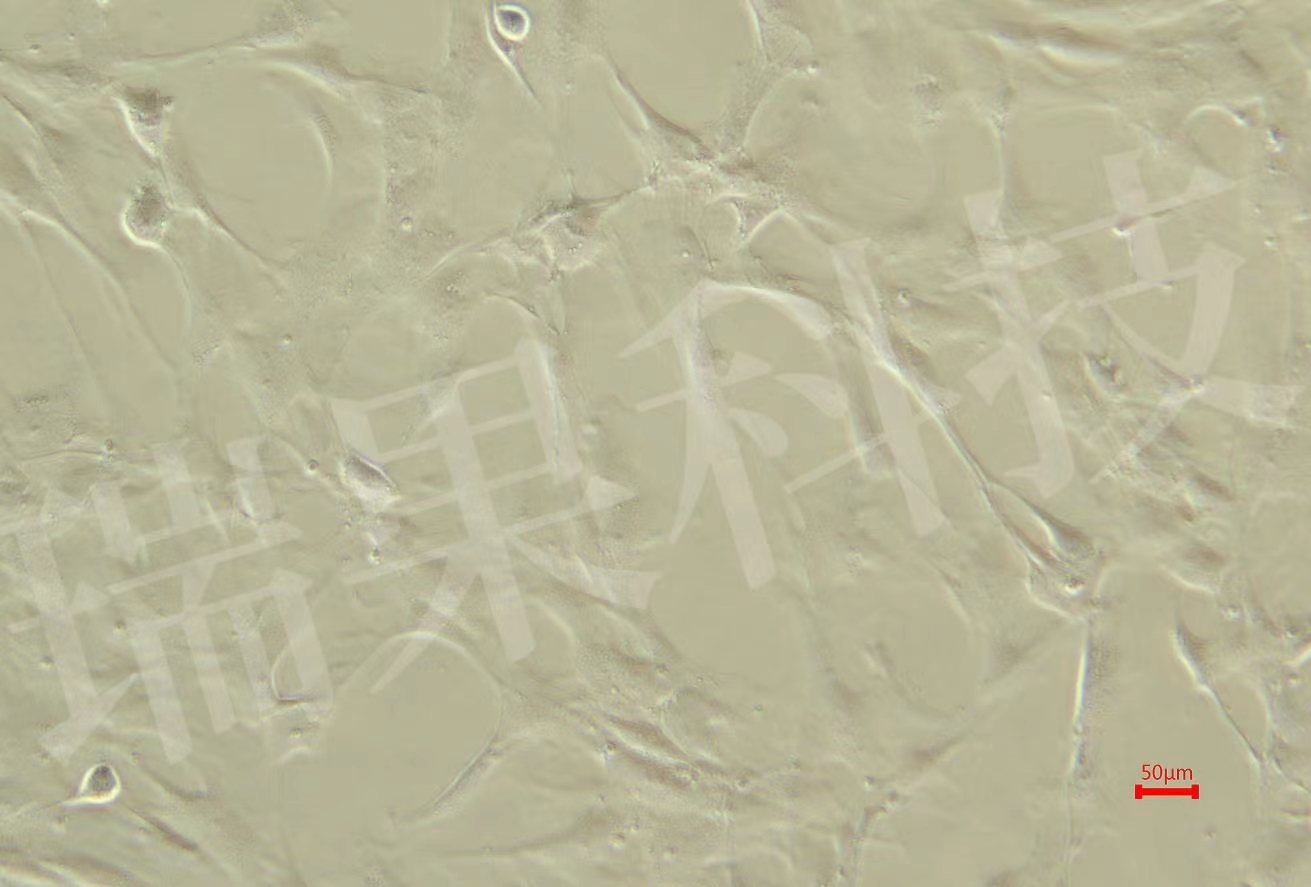

巨噬細胞是顯著的可塑性細胞,可以從一種表型轉換到另一種表型...